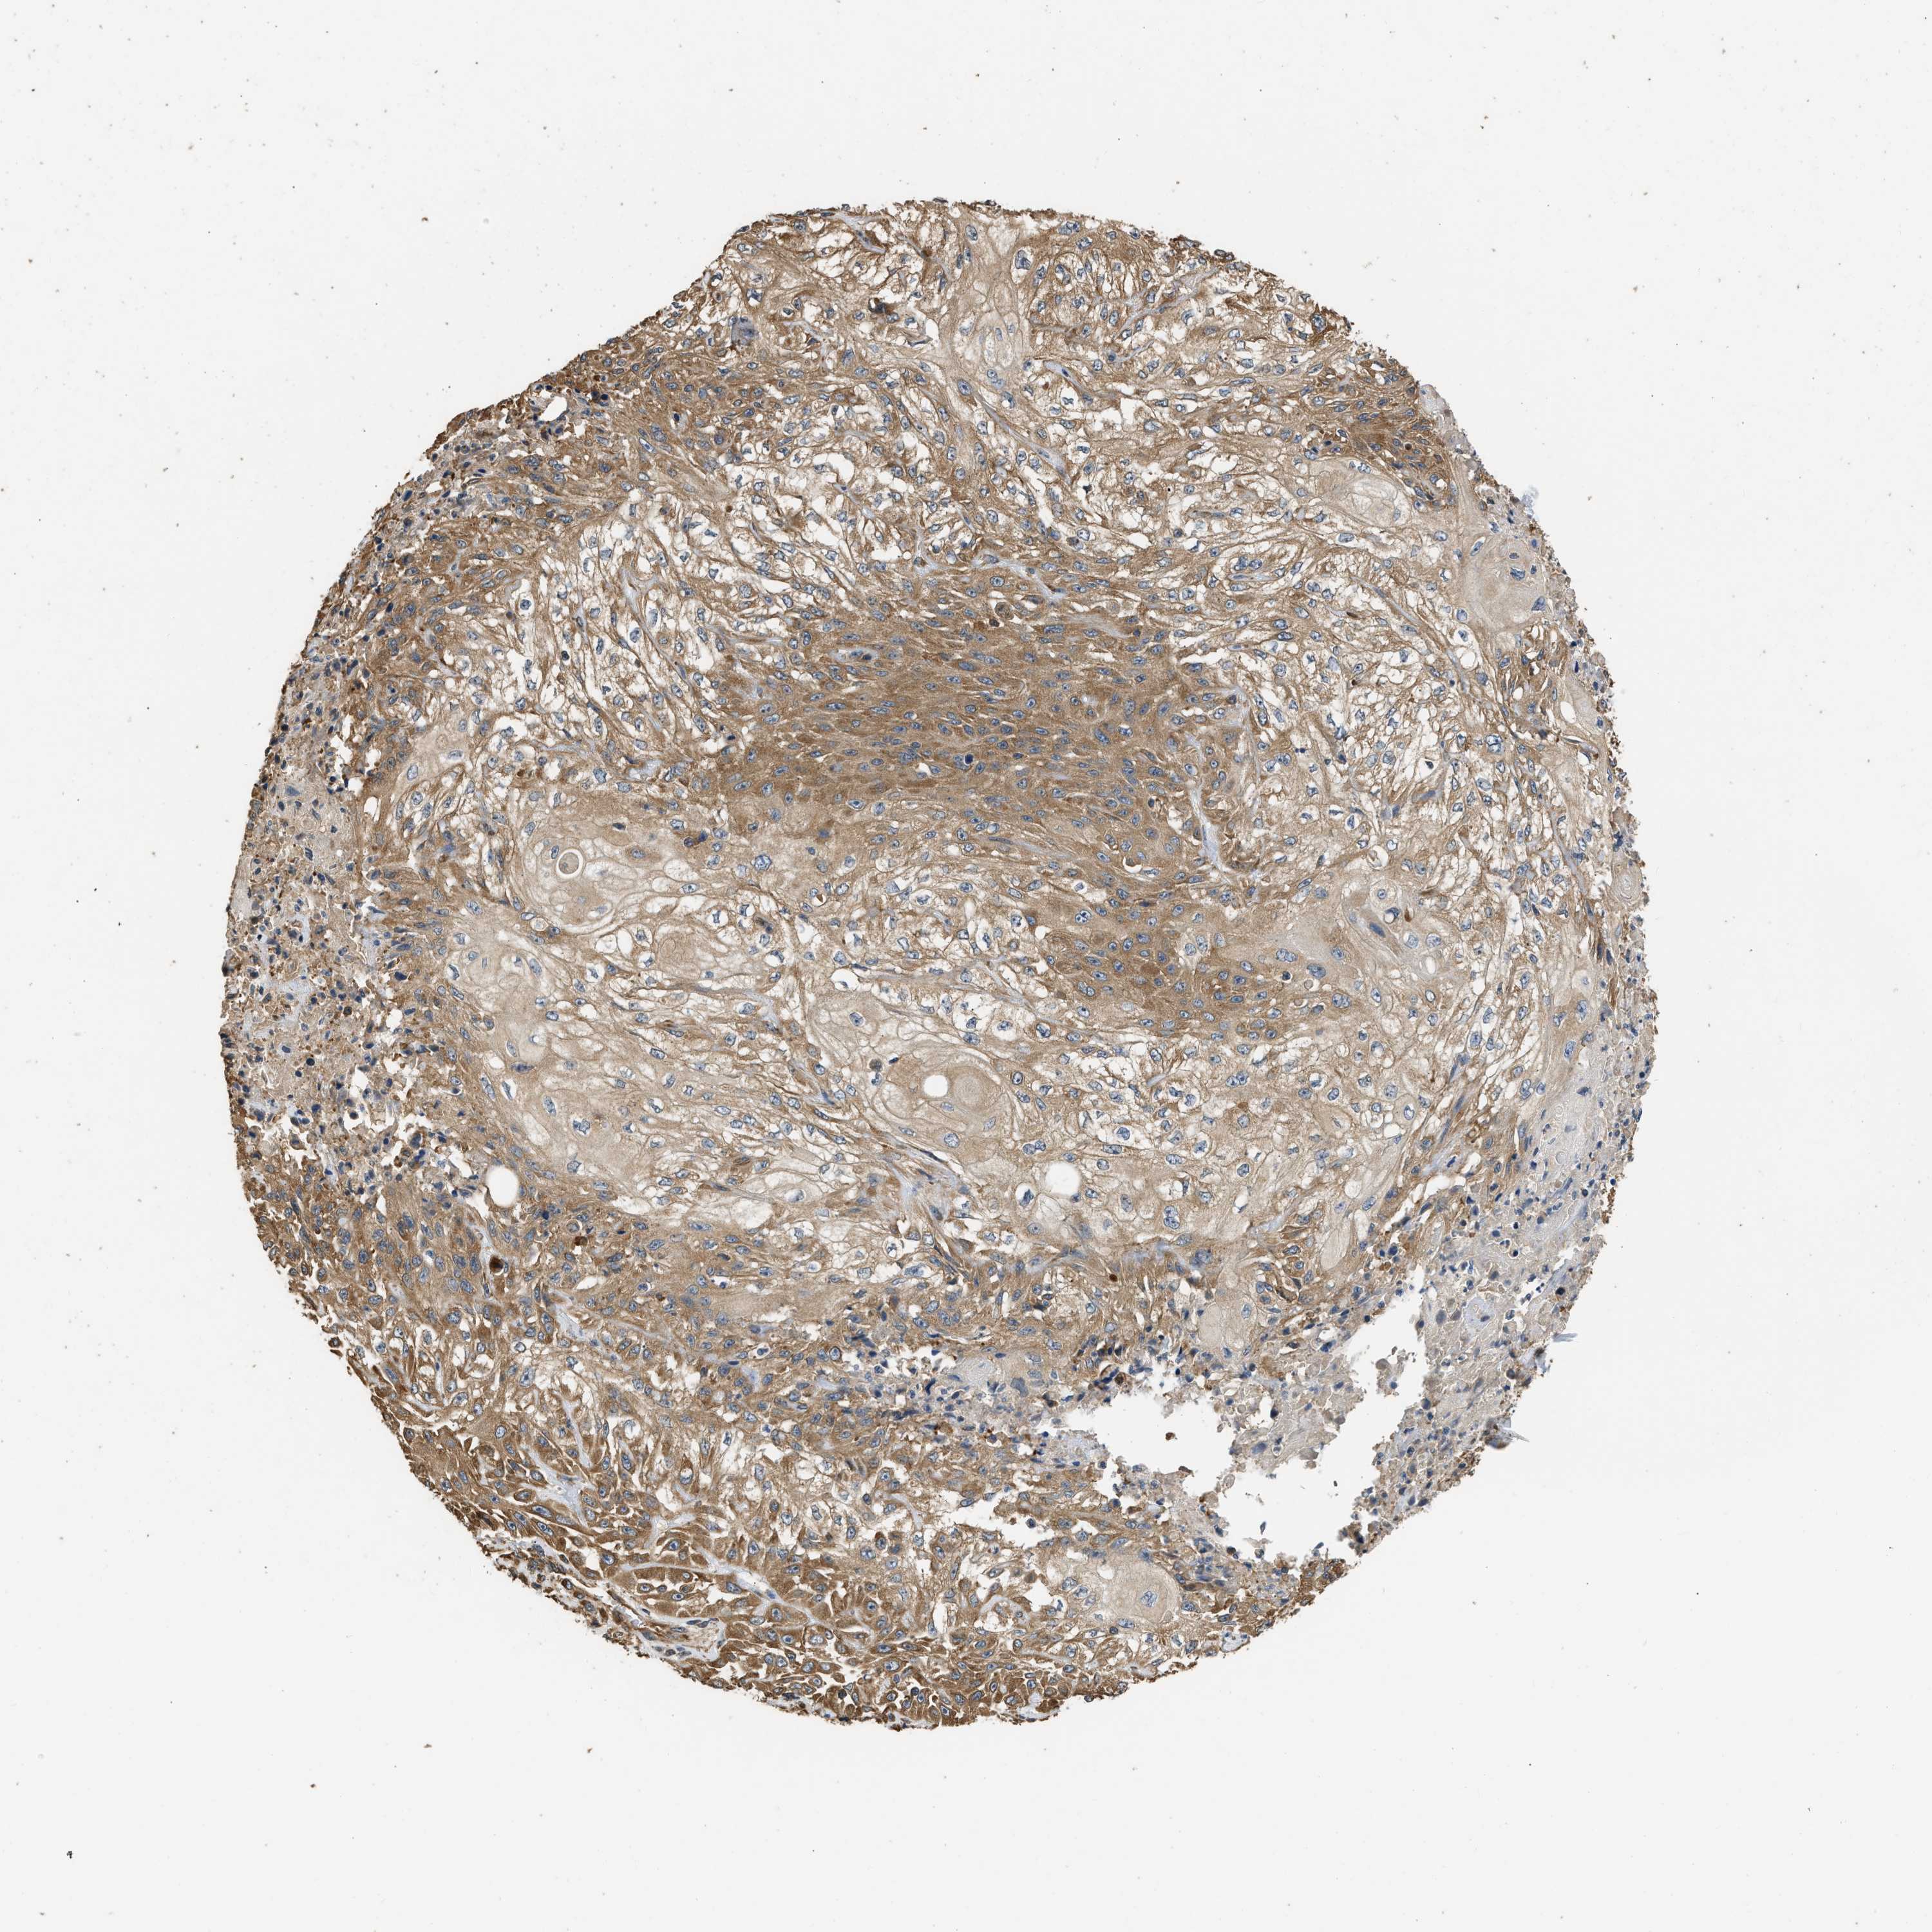

SKIN CANCER - Protein expressioni

A mouse-over function shows sample information and annotation data. Click on an image to view it in a full screen mode. Samples can be filtered based on level of antibody staining by selecting one or several of the following categories: high, medium, low and not detected. The assay and annotation is described here.

Antibody stainingi

Antibody staining in the annotated cell types in the current human tissue is reported as not detected, low, medium, or high, based on conventional immunohistochemistry profiling in selected tissues. This score is based on the combination of the staining intensity and fraction of stained cells.

Each image is clickable and will lead to virtual microscopy that enables deeper exploration of all samples and also displays staining intensity scores, fraction scores and subcellular localization as well as patient and tissue information for each sample.

Antibody HPA017887

Staining

High

Intensity

Strong

Quantity

>75%

Location

Cytoplasmic/membranous

Squamous cell carcinoma, NOS